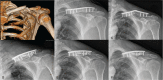

Open reduction and pre-contoured locking plate fixation is a popular treatment option for displaced midshaft clavicle fracture. Lag screw and cerclage are 2 main intraoperative techniques to reduce and fix fragments. However, both lag screw and metallic cerclage have disadvantages. The doubled-suture Nice knot has been reported in many areas of orthopedic surgery for its effectiveness. This study aims to compare the outcomes of comminuted mid-shaft clavicle fractures reduced by Nice knots vs traditional techniques (lag screw or/and metallic cerclage) when bridged with pre-contoured locking plates.We retrospectively reviewed 101 patients (65 females and 36 males) diagnosed with midshaft clavicle fractures with at least one wedge fragment reduced by either Nice knots or traditional methods and bridged with pre-contoured locking plates between December 2016 and April 2019. Operation time, functional outcomes, pain, patient satisfaction, fracture healing, and complications were assessed at a follow-up of 12 to 40 months.The mean age of all the patients was 50.8 years. There were 52 and 49 patients in the Nice knot group and traditional group respectively, and no differences between 2 groups were found in general patient characteristics, fracture type, follow up and injury-to-surgery duration. The Nice knot group had significant less operation time (P < .01) than the traditional group (mean and standard deviation [SD], 78.6 ± 19.0 compared with 94.4 ± 29.9 minutes, respectively). For healing time, functional score, pain, satisfaction and complications, there were no significant differences between groups, despite the Nice knot group had slightly better results.Both Nice knots and traditional methods treated for comminuted Robinson type 2B clavicle fractures were effective and safe. And the Nice knots seemed to be superior with significant less operation time.